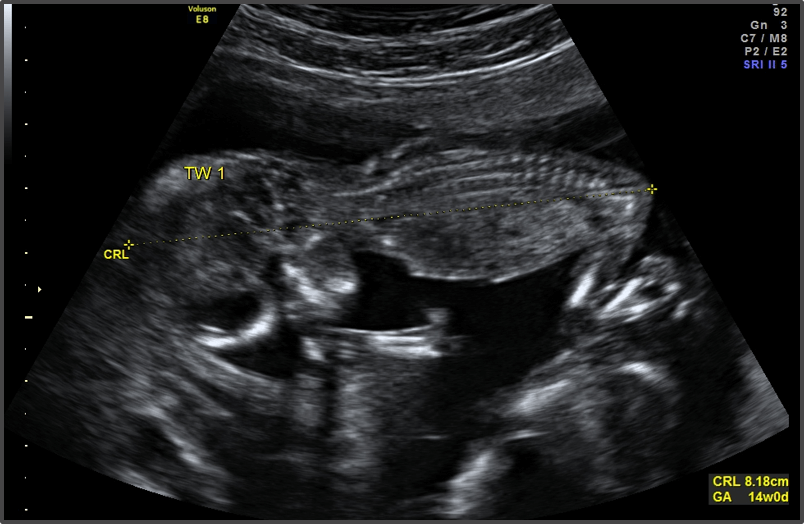

The baby is now the size of a lemon.

Baby is the size of Peach

Approx Baby Weight: 43g

Approx Baby Size: 8.7 cm